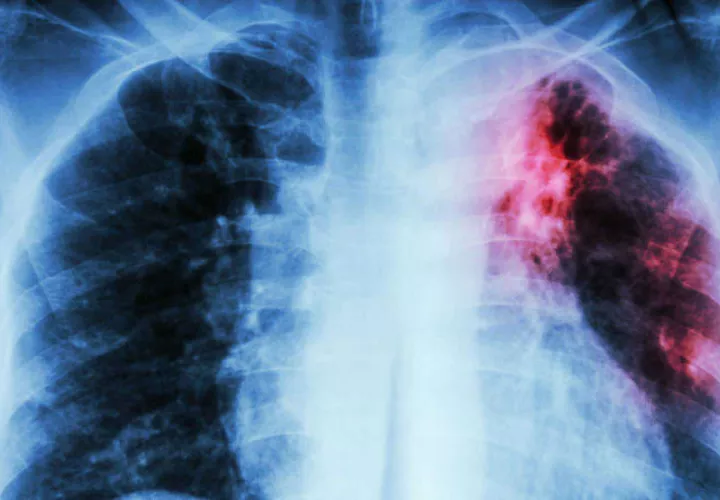

Médicos contagiados por tuberculosis

El Ministerio de Salud reportó que hay dos médicos residentes del hospital Santo Tomás afectados con tuberculosis. Se encuentran incapacitados y su condición de salud es estable.

En lo que va del año 2019, el programa encargado de este enfermedad registra 1,450 casos de tuberculosis a nivel nacional y las regiones con mayor incidencia de casos son la provincia de Bocas del Toro, Guna Yala y Panamá Este, por lo que se mantiene el control y vigilancia.